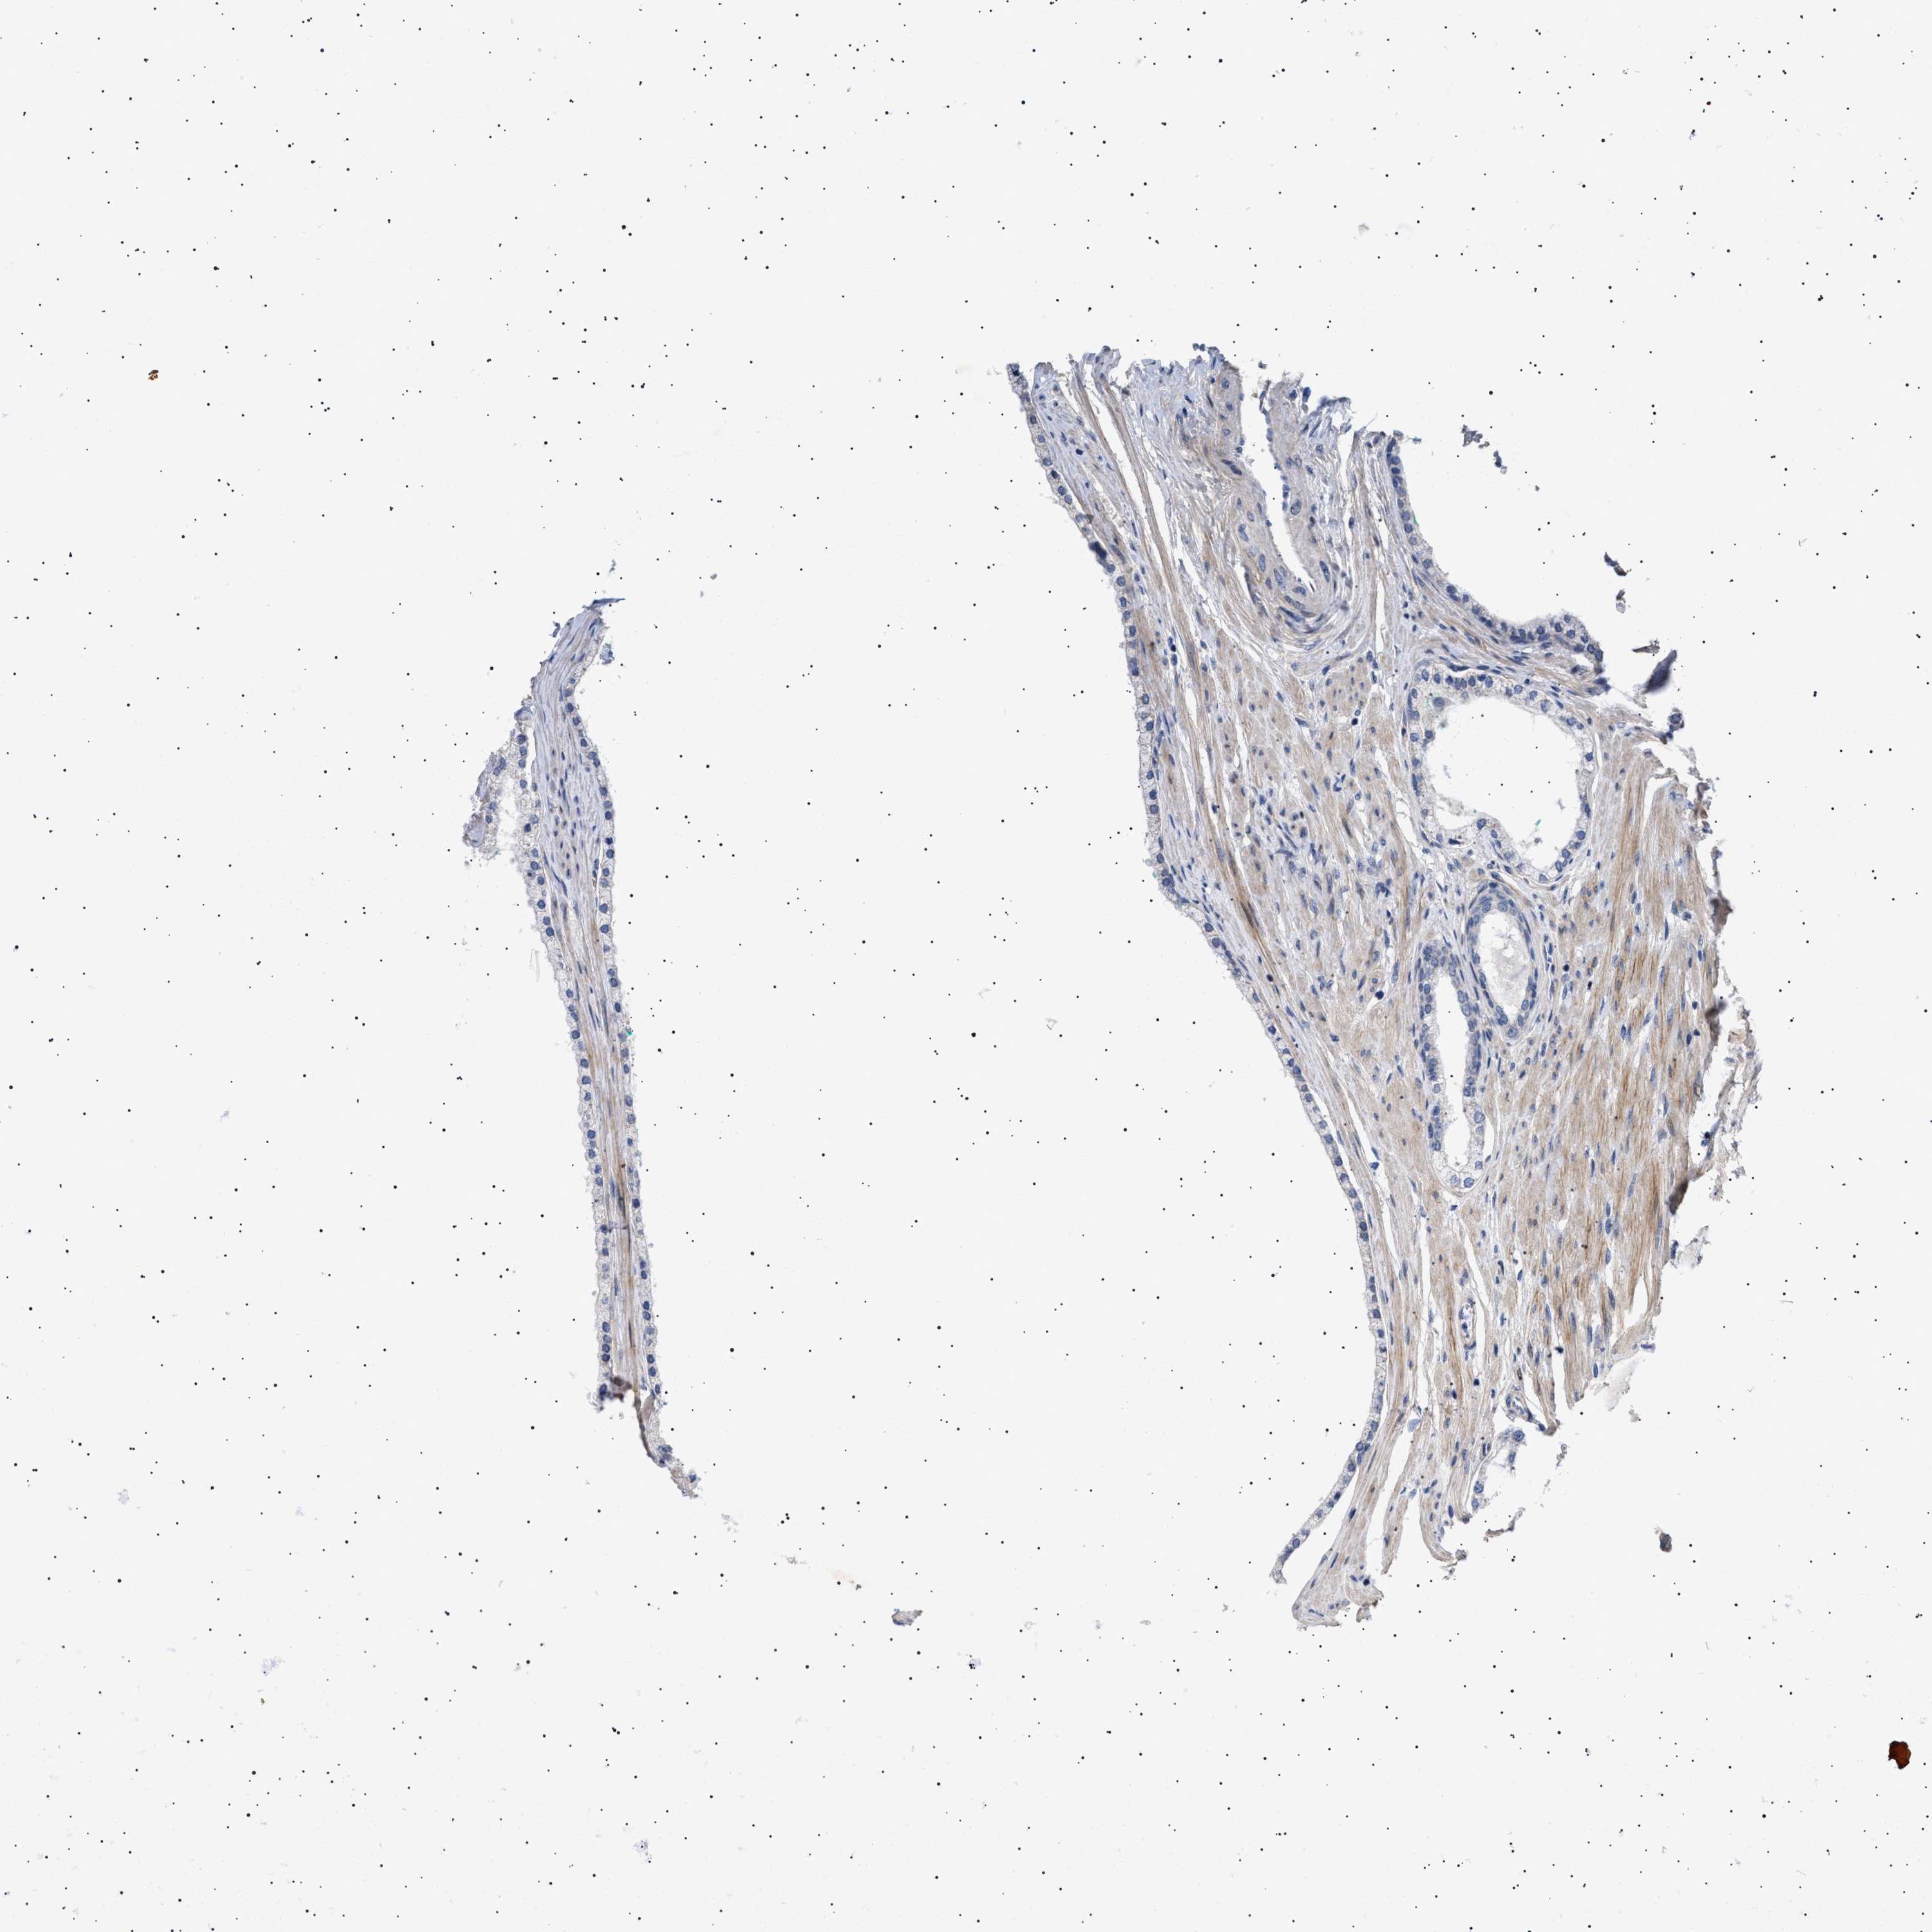

PROSTATE CANCER - Protein expressioni

A mouse-over function shows sample information and annotation data. Click on an image to view it in a full screen mode. Samples can be filtered based on level of antibody staining by selecting one or several of the following categories: high, medium, low and not detected. The assay and annotation is described here.

Note that samples used for immunohistochemistry by the Human Protein Atlas do not correspond to samples in the TCGA dataset.

Antibody stainingi

Antibody staining in the annotated cell types in the current human tissue is reported as not detected, low, medium, or high, based on conventional immunohistochemistry profiling in selected tissues. This score is based on the combination of the staining intensity and fraction of stained cells.

Each image is clickable and will lead to virtual microscopy that enables deeper exploration of all samples and also displays staining intensity scores, fraction scores and subcellular localization as well as patient and tissue information for each sample.

Antibody HPA018073

Staining

High

Medium

Low

Not detected

Intensity

Strong

Moderate

Weak

Negative

Quantity

>75%

75%-25%

<25%

None

Location

Nuclear

Cytoplasmic/membranous

Cytoplasmic/membranous,nuclear

Adenocarcinoma, High grade

Adenocarcinoma, Low grade